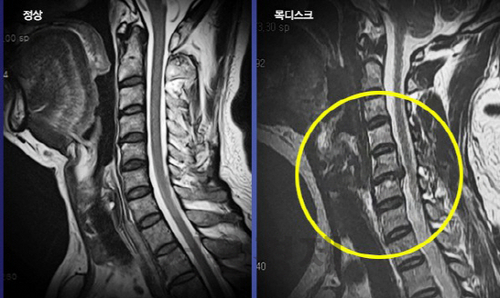

목 디스크는 목의 디스크(경추 디스크)에서 출현하는 질환으로, 경추 디스크 사이의 연골판이 터져 디스크 내부 물질이 경추 신경을 자극해 통증이나 저림증 등의 증상을 유발 해요. 목 디스크는 일상생활에서의 안 좋은 자세나 많은 운동, 부상 등이 이유가 되는 것이 될 수 있기도하고, 시간이 지날수록 발생 확률이 높아져요. 목 디스크의 증상으로는 목 부위의 통증, 팔의 저림, 근육 약화 등이 있으며, 증상이 난폭한 경우 수술 등의 치료가 필요할 수 있어요. 그리하나 대개의 경우 치료 없이도 시간이 지나면 증상이 호전되는 경우가 대부분입니다.

목디스크 증상 목 자세이고요. 현대인들은 스마트폰이나 모니터를 많이 사용하다보니 목이 앞쪽으로 당겨져있는 것처럼 자세를 많이 취하게 된다 하였습니다. 이런 자세는 정상적인 목뼈를 전환 시켜 여러분이 아시는 거묵목 증상이 나타나게 되는 이유가 되는 것입니다.